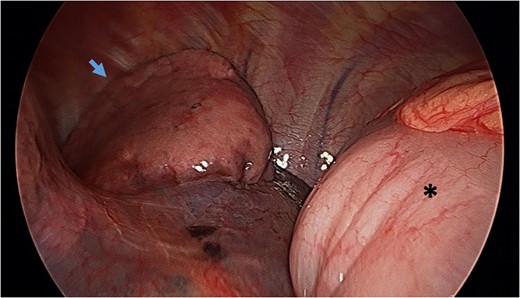

Video-assisted thoracoscopy (VAT) demonstrating a loop of transverse colon in the left hemithorax. Black asterisk (*) indicates a loop of transverse colon. Blue arrow indicates deflated left lung.

Reduction of transverse colon into abdominal cavity. The spleen is visible adjacent to the transverse colon. Black asterisk (*) indicates a loop of transverse colon. Blue broken arrow indicates the diaphragmatic defect that was extended to successfully reduce the colon.